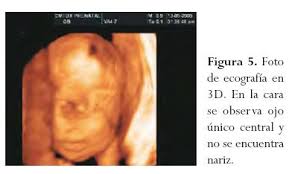

KILU escribió:Pocas ecografías habéis visto

¿De estas cuantas has visto tu?

Los niños sin nariz también tienen derecho a (mal)vivir.

Hostia, qué mal cuerpo se me está quedando con las fotos... Y aún se habla de aborto eugenésico como si por tener una peca en la nariz fusilasen al feto.